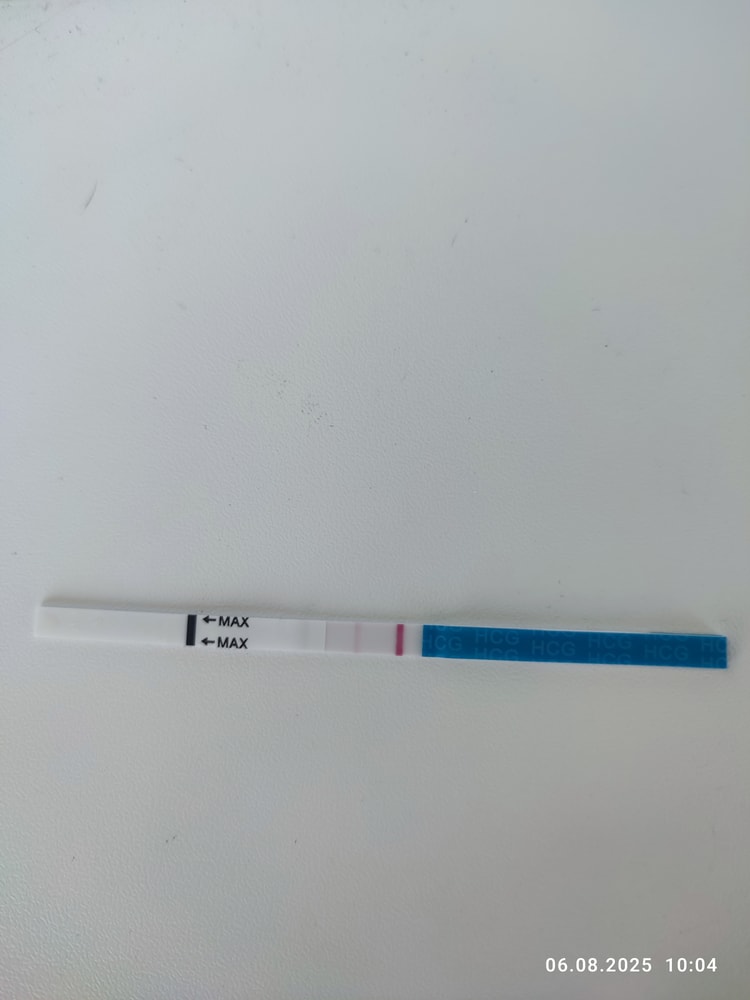

Первые два мама чек

Мне кажется у эвика что-то есть, но надо повторить однозначтно

Мария Кот, я тоже на эвике вижу, но надо смотреть дальше